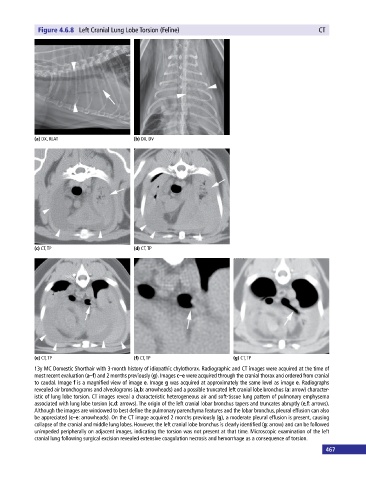

Figure 4.6.8 Left Cranial Lung Lobe Torsion (Feline) CT

13y MC Domestic Shorthair with 3‐month history of idiopathic chylothorax. Radiographic and CT images were acquired at the time of

most recent evaluation (a–f) and 2 months previously (g). Images c–e were acquired through the cranial thorax and ordered from cranial

to caudal. Image f is a magnified view of image e. Image g was acquired at approximately the same level as image e. Radiographs

revealed air bronchograms and alveolograms (a,b: arrowheads) and a possible truncated left cranial lobe bronchus (a: arrow) character-

istic of lung lobe torsion. CT images reveal a characteristic heterogeneous air and soft‐tissue lung pattern of pulmonary emphysema

associated with lung lobe torsion (c,d: arrows). The origin of the left cranial lobar bronchus tapers and truncates abruptly (e,f: arrows).

Although the images are windowed to best define the pulmonary parenchyma features and the lobar bronchus, pleural effusion can also

be appreciated (c–e: arrowheads). On the CT image acquired 2 months previously (g), a moderate pleural effusion is present, causing

collapse of the cranial and middle lung lobes. However, the left cranial lobe bronchus is clearly identified (g: arrow) and can be followed

unimpeded peripherally on adjacent images, indicating the torsion was not present at that time. Microscopic examination of the left

cranial lung following surgical excision revealed extensive coagulation necrosis and hemorrhage as a consequence of torsion.